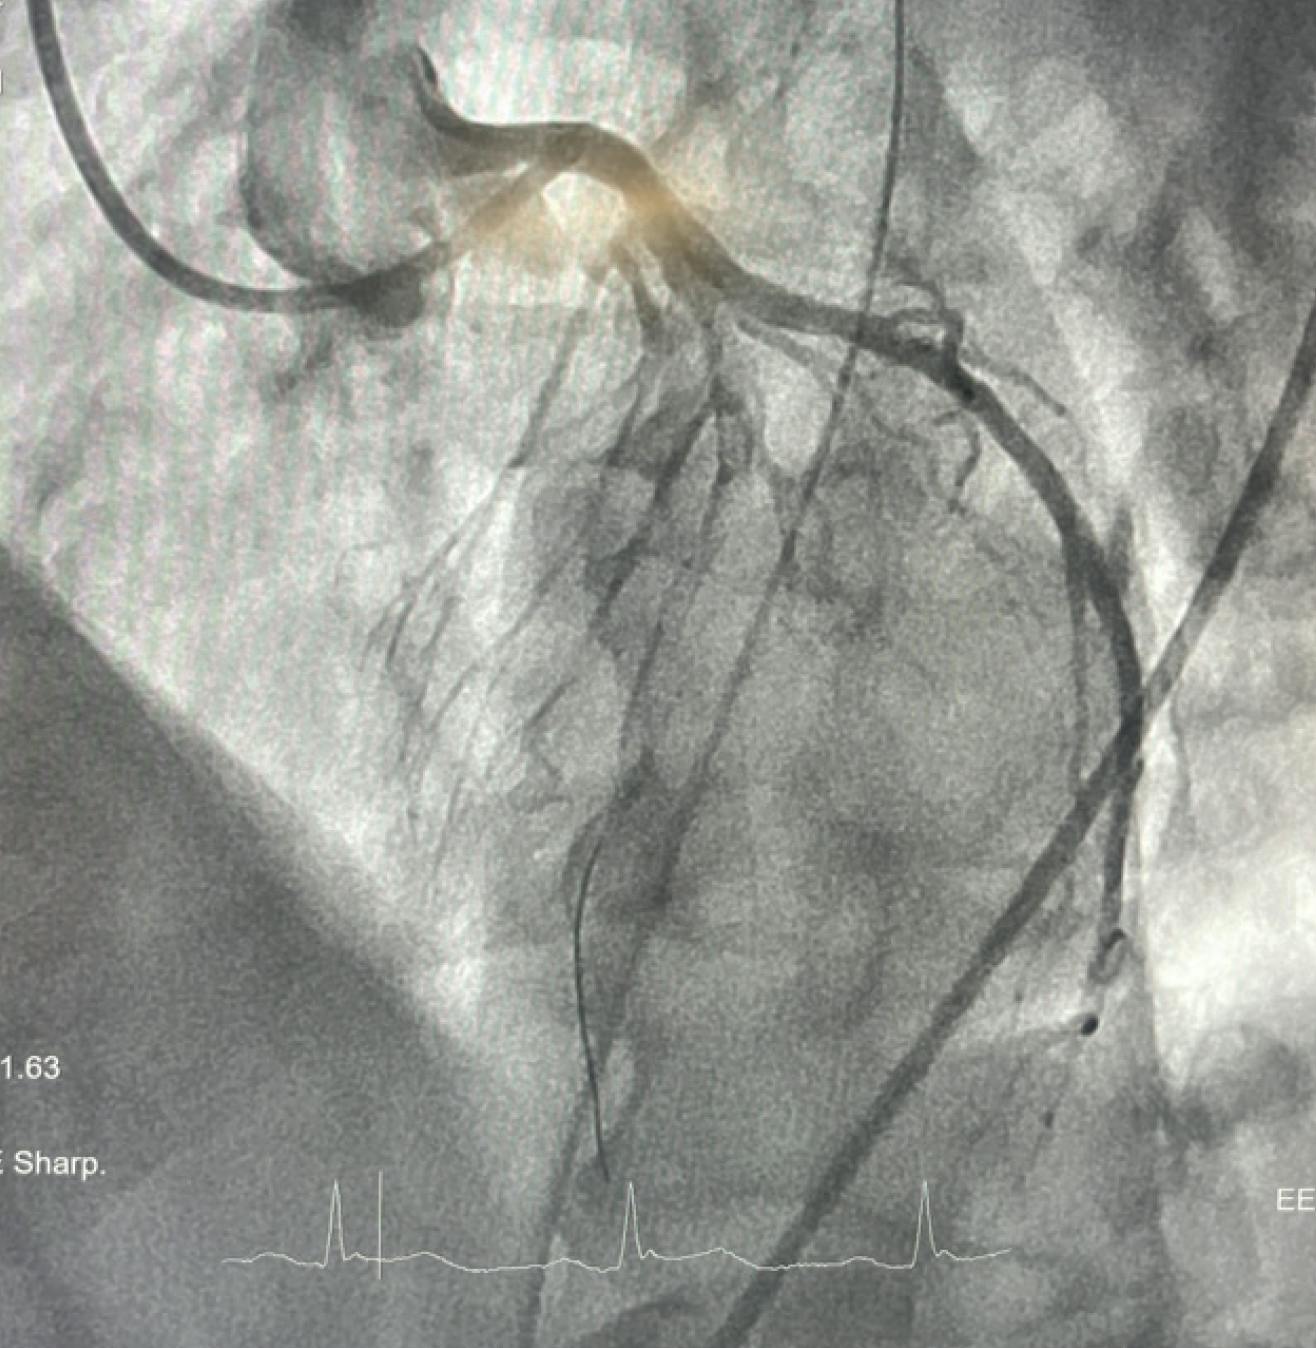

The duration of the cardiac arrest was > 45 minutes, but the emergency responders were present at onset and the patient received consistent compressions throughout. Further tests were ordered, identifying a segment just beyond the ostium of the left anterior descending (LAD) artery that was completely filled with thrombus, extending all the way to the distal vessel (Figure 1). The patient was suspected to have experienced a complete occlusion several hours earlier and had been accumulating thrombus since.

Figure 1. Initial angiogram of the LAD.

Despite initial balloon angioplasty, revascularization was unsuccessful. Next, manual aspiration catheter was utilized to address the clot burden; however, this was also unsuccessful. The team pivoted to use of the CAT RX aspiration system (Penumbra, Inc.) to deliver sustained power aspiration. In conjunction with the Penumbra ENGINE™ (Penumbra, Inc.), CAT RX removed approximately 95% of the thrombus in two passes. Subsequently, with the use of intravascular ultrasound, the patient’s LAD was stented (Figure 2). After the procedure, the patient was noted to have severely reduced LV function and hypotension. The patient was placed on vasopressors and inotropic support via intravenous infusions and, ultimately, mechanical circulatory support via an Impella device (Abiomed, Inc.). Roughly 48 hours later, the patient was taken off all circulatory support and infusions due to improved hemodynamics and recovered LV function, with repeat echocardiography demonstrating an LV ejection fraction > 65%.

Figure 2. Final angiogram after thrombectomy and stenting.